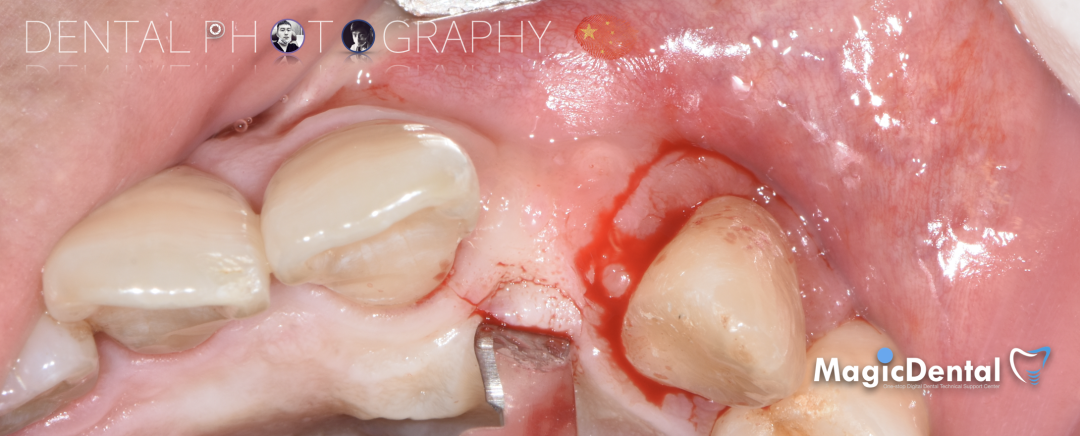

患者术前口内照片

40岁男性患者。

主诉:左上前牙缺失求修复。

现病史:患者因外伤导致前牙松动半年之久,两个月前于外院拔除左上前牙,现自觉不美观来我院就诊。

既往史:既往体健,无其他系统病史,否认重大疾病史,有口腔拔牙史。口腔检查:口腔卫生良好,牙周状况良好,22缺失,缺失间隙约7mm,CT显示缺失牙位置唇颚侧骨壁薄,无对颌伸长,邻牙无移位,上下前牙呈深覆 ,38、48近中阻生。

切开翻瓣,彻底暴露术区,试戴骨块。